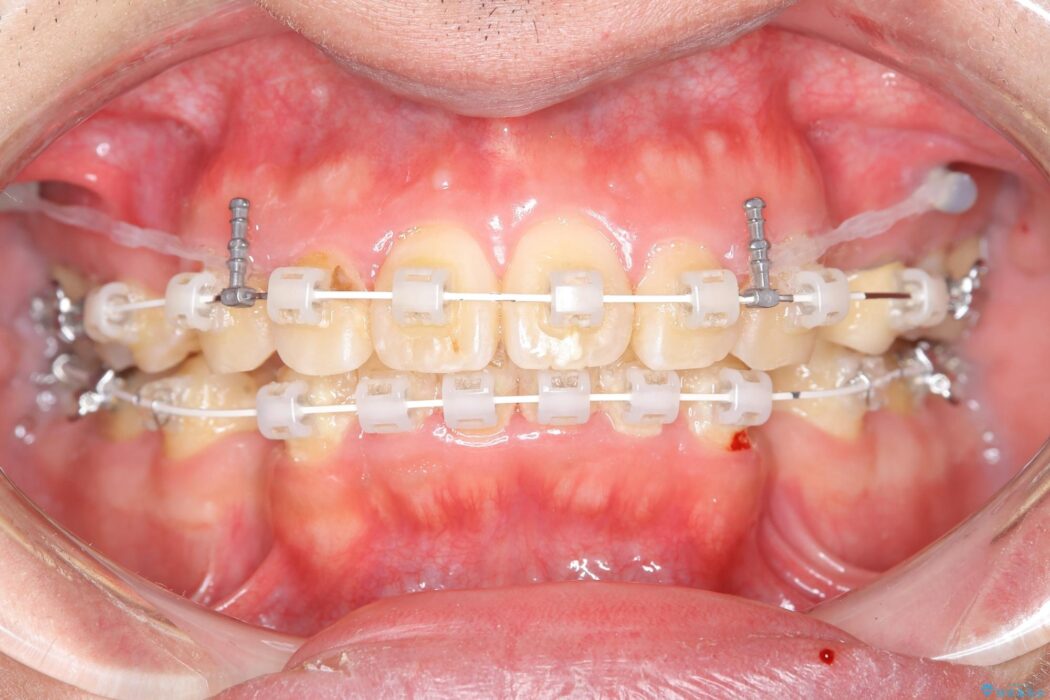

抜歯でスペースができるため、歯の移動量が多いことから表側ワイヤー矯正装置で治療を行いました。

ワイヤー矯正、マウスピース矯正、それぞれの特性、得意な治療がありますので、患者様の状態に合わせた治療器具の選択が大事となります。